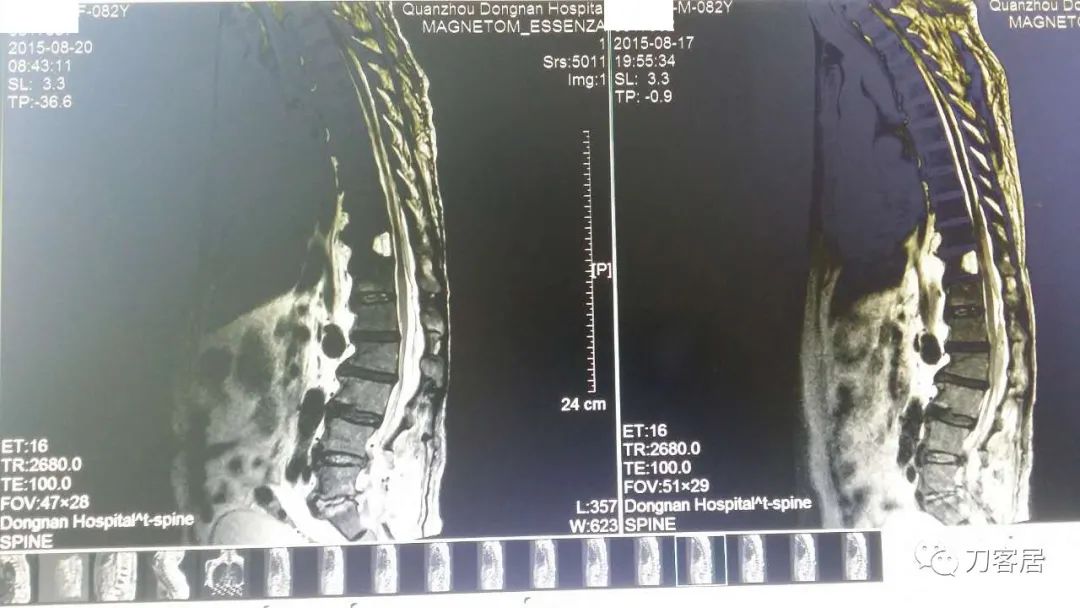

加注图23. 8月20日复查腰椎MRI,血肿占位缩小。

加注图24. 8月20日复查腰椎MRI,血肿占位缩小。

教授,早上好!这是上午刚复查的磁共振,血肿小多了。左腿还是有酸痛,这两天比刚穿刺完明显,但是肌力还是好的。

这是今天和前天片子比较,我放一起比较看比较直观。

加注图25. 8月20日腰椎MRI与17日MRI对比。(此图与加注图26是一样的)

加注图26. 8月20日腰椎MRI与17日MRI对比。(此图与加注图25是一样的)

加注图27. 8月20日腰椎MRI与17日MRI对比。上面的日期清晰一些。

左边是现在,右边是3天前。上面有时间。我放一起好比较 , 观片工作站有对比模式。